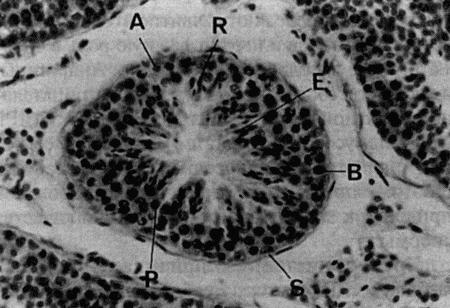

Стадия проэструса характеризуется развитием фолликулов под влиянием гонадотропных гормонов — лютеинизирующего (ЛГ) и фолликулостимулирующего (ФСГ), выделяемых передней долей гипофиза. Секреция этих гормонов регулируется гипоталамическим гонадотропинрилизинг гормоном (ГнРГ). У собак, так же, как и у других животных, вслед за пиком концентрации эстрадиола возникает (спустя сутки или чуть больше) пик концентрации ЛГ (фиг. 1.1). Таким образом, выброс ЛГ происходит всегда автоматически вслед за повышением активности фолликулов, вырабатывающих эстрадиол, и поскольку овуляция следует за возникающим без внешней стимуляции пиком концентрации ЛГ, ее называют спонтанной. Описанная ситуация разительно отличается от картины, которую можно наблюдать у кошек, для которых характерна индуцированная овуляция: у них выброс ЛГ и овуляция происходят вслед за коитусом. Насколько можно судить, у таких животных эстрадиол не способствует активации секреции ЛГ.

Повышение уровня ФСГ необходимо для стимуляции развития фолликулов и секреции эстрадиола, однако концентрация ФСГ в крови не достигает столь высоких значений, какие наблюдаются при пике ЛГ; это объясняют действием ингибина — белка, секретируемого фолликулами, который избирательно подавляет секрецию ФСГ Тем не менее ФСГ играет важную роль в созревании фолликулов и подготовке их к трансформации в желтые тела после овуляции. Начало трансформации фолликулярных клеток рассматривают как ключевой момент всего цикла, поскольку оно сопровождается преовуляторным повышением секреции прогестерона (фиг. 1.1), которое, по-видимому, играет ведущую роль в пусковом механизме овуляции и подтверждении эструса. Наблюдаемый у собак преовуляторный рост концентрации прогестерона нетипичен для других домашних животных, в частности для жвачных, у которых наступление эструса и овуляции происходит на фоне минимального уровня прогестерона. Однако преовуляторная концентрация прогестерона у собак все же относительно низка, и следует помнить, что назначение высоких доз прогестагенов в период проэструса вызывает отсрочку эструса и овуляции.

Как правило, у сук наблюдается множественная овуляция; согласно данным гистологических и лапароскопических исследований, в большинстве случаев овуляция происходит в течение 30–48 часов после пика концентрации ЛГ, хотя часть фолликулов овулируют лишь через 96 часов. После овуляции, но до оплодотворения ооциты проходят очередную стадию мейоза. Этот процесс с трудом поддается изучению, однако тщательный хронометраж искусственного осеменения замороженной спермой, взятой от разных кобелей (для упрощения идентификации потомства), приводит к выводу, что созревание ооцитов занимает 2–3 дня. Если сложить их с количеством дней, отделяющих пик концентрации ЛГ от овуляции, то получится, что оплодотворение возможно не раньше, чем через 4 дня, считая от пика концентрации ЛГ; этот день является началом фертильного периода (фиг. 1.2). Ошибки в его вычислении объясняются тем, что признаки эструса наблюдаются уже за 5 дней до начала фертильного периода и продолжаются еще 5 дней после его окончания. Следующие факторы определяют длительность фертильного периода: длительное (до нескольких дней) сохранение жизнеспособности спермы в половом тракте суки; время, необходимое для овуляции и созревания ооцитов (2–3 дня) при сохранении жизнеспособности яйцеклеток (1–2 дня). С учетом этих факторов фертильным следует признать период, продолжающийся от 4-го до 7-го дня, считая от пика концентрации ЛГ. При стандартном подсчете продолжительность беременности составляет от 58 до 72 дней, но если принять за точку отсчета овуляторный пик ЛГ, длительность беременности составит 65 дней с очень небольшими отклонениями.